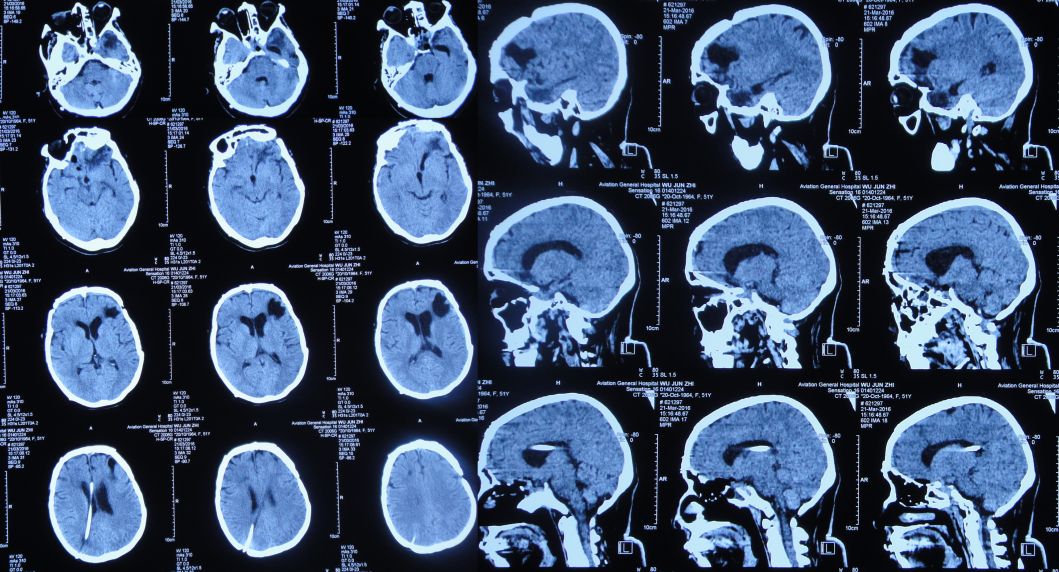

分流术后第18天即2016年3月21日,患者神清,精神可,生活自理;复查头CT显示垂体窝周围积气(图55),考虑脑脊液鼻漏复发可能。

图55:2016年3月21日头CT:垂体窝周围积气

分流术后第60天即2016年5月4日,患者神清,精神可,生活自理;复查头CT显示脑室恢复正常,颅内无积气(图56),办理出院。

图56:2016年5月4日头CT:脑室恢复正常,颅内无积气

出院后6个月即2016年10月24日来院复查,患者神清,精神好,思维及肢体活动完全恢复正常(图57)。复查头CT:脑室正常,颅内无积气(图58)。

图58:2016年10月24日头CT:脑室恢复正常,颅内无积气